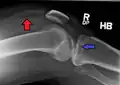

![]() | |

| A severe tibial plateau fracture with an associated fibular head fracture | |